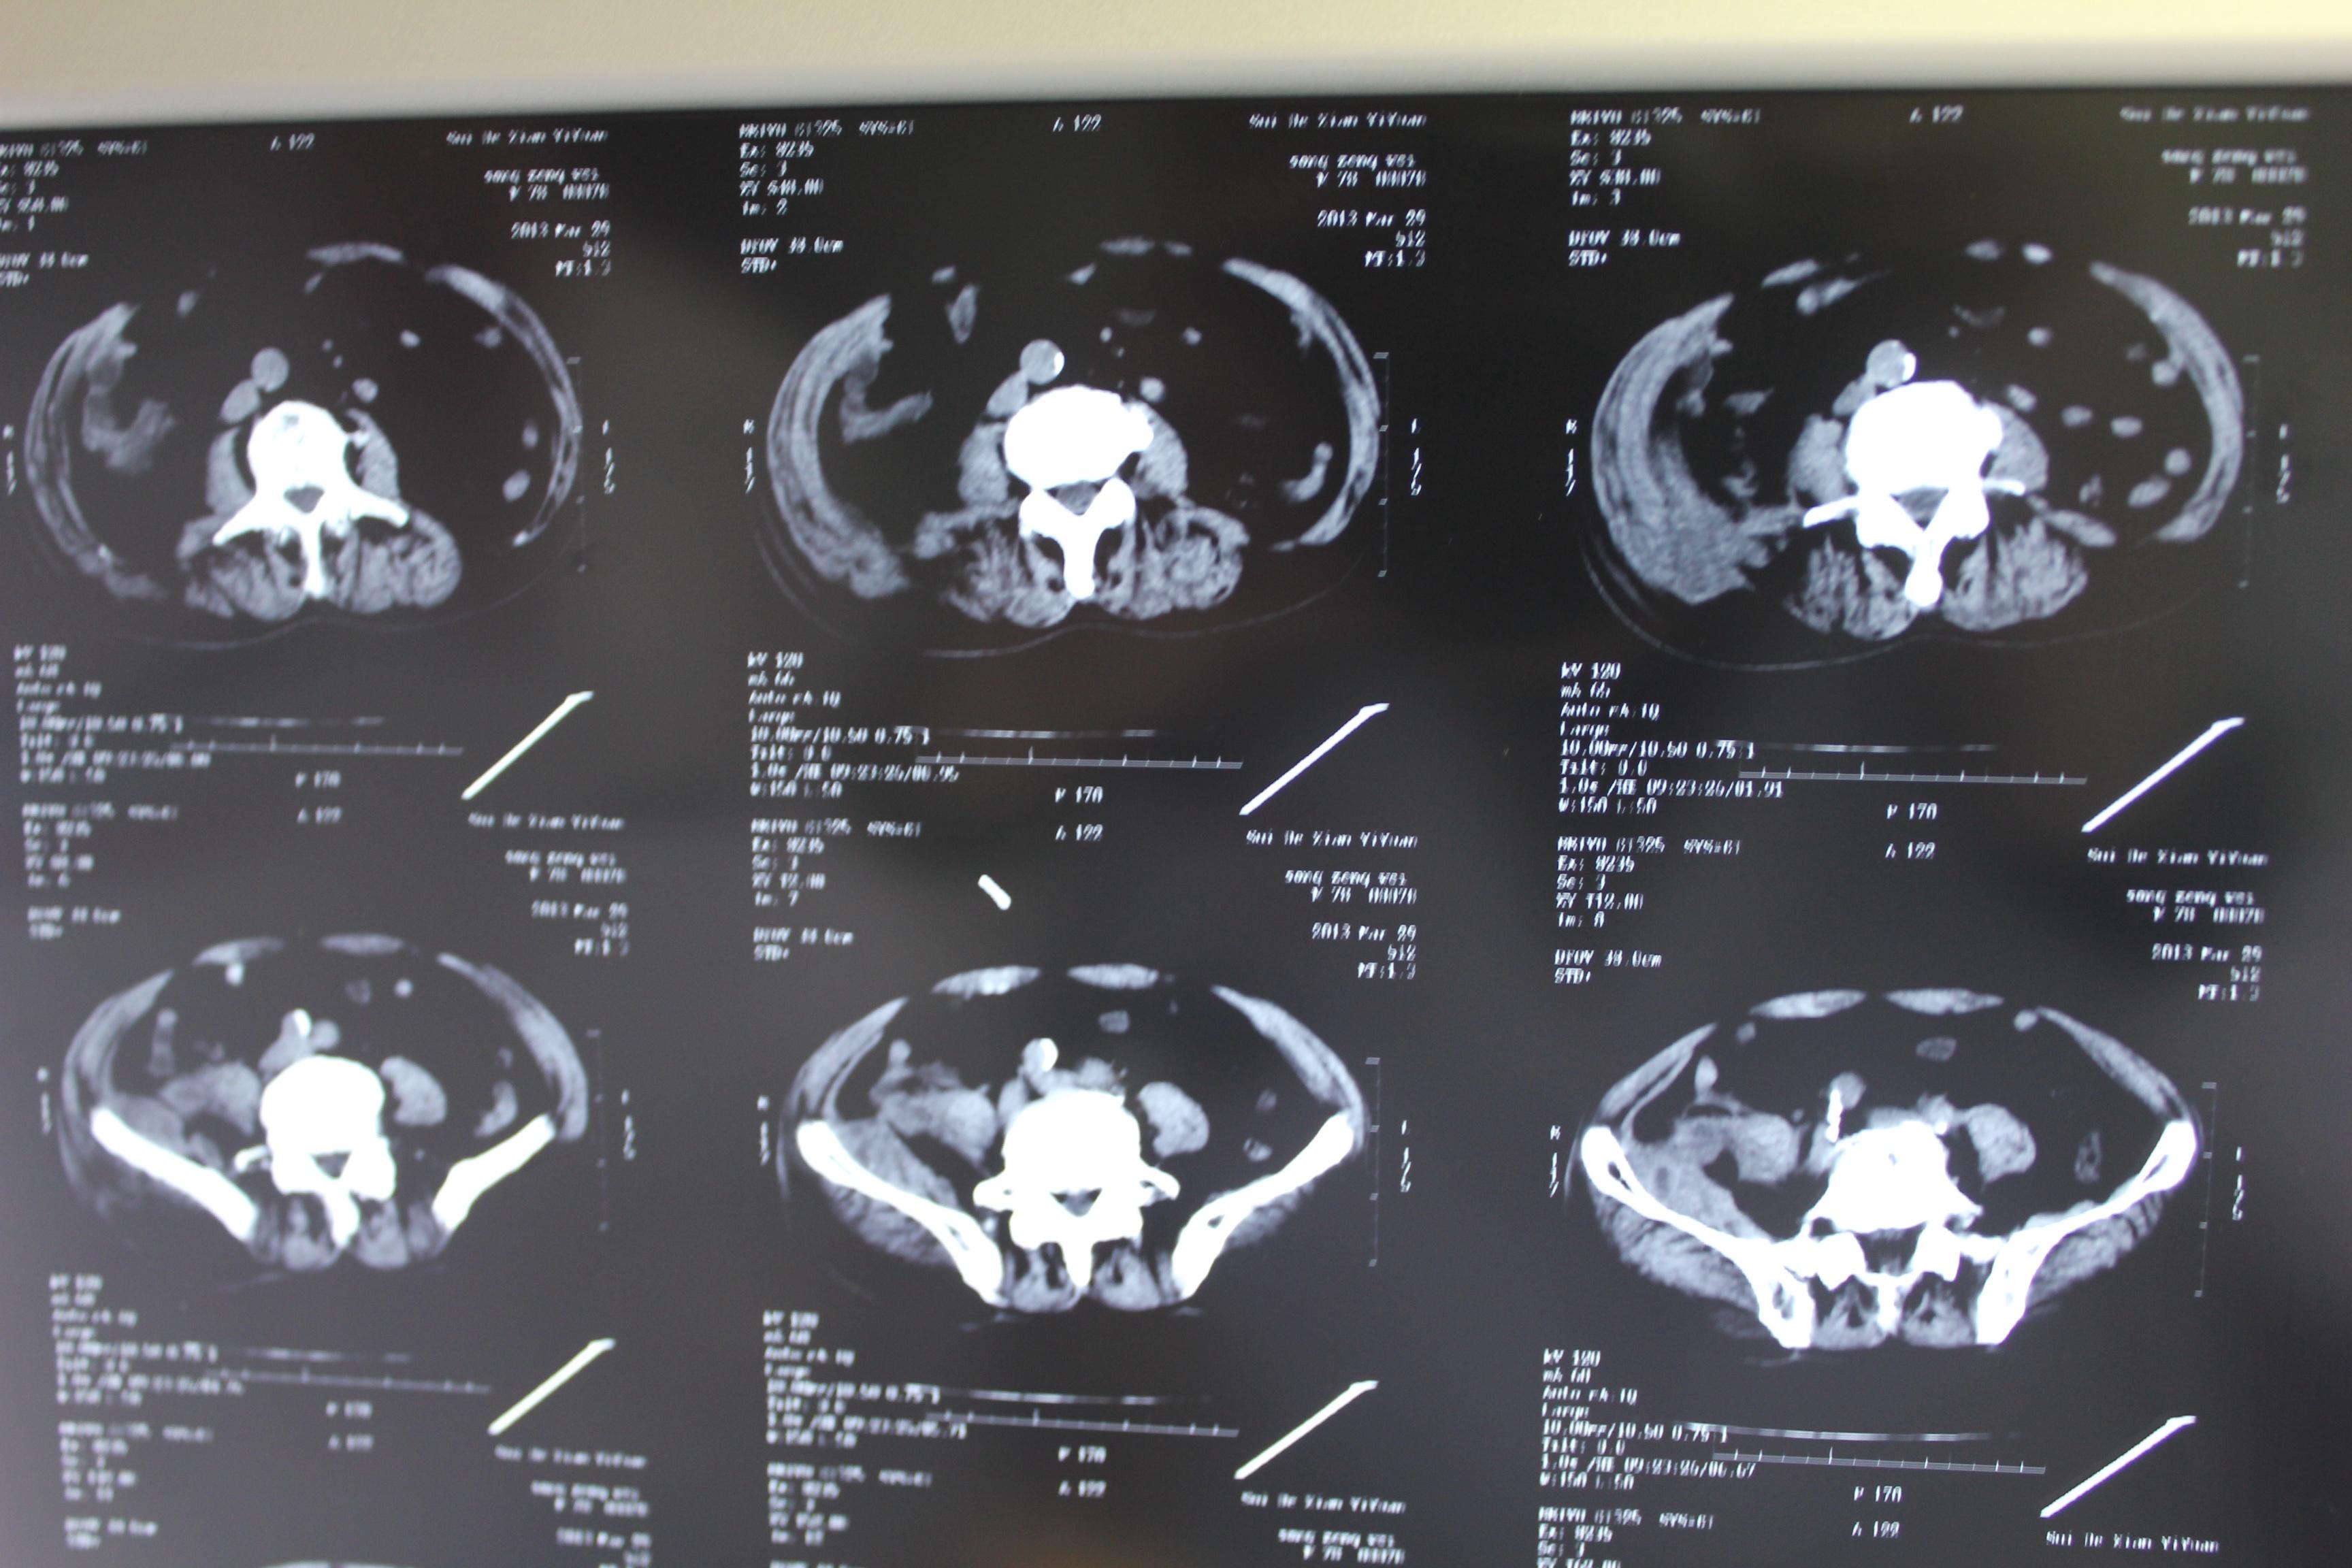

老年患者78岁,反复腰背部溃烂流脓4年,既往30年前曾在包块处排出蛔虫一条。CT:

明日手术探查